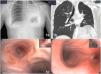

Our patient was a 24-year-old woman with a previous diagnosis of pulmonary tuberculosis. After 4 months of treatment with rifampicin+isoniazid and 2 months with rifampicin+isoniazid+pyrazinamide+ethambutol with good adherence, she showed clinical improvement, radiological improvement, and negative sputum smear microscopy and culture. She presented due to sudden onset of dyspnea, pleuritic chest pain, and desaturation. X-ray was performed (Fig. 1a), revealing consolidation with atelectasis of practically the entire left lung. Chest computed tomography (CT) (Fig. 1b) showed complete occlusion of the lumen with occupation extending to the anterior segmental bronchus, the lingula, and the left lower lobe with secondary atelectasis. Stenosis was confirmed by bronchoscopy (Fig. 1c and d) and a diagnosis of endobronchial tuberculosis was confirmed by lung biopsy. Cryotherapy and corticosteroid therapy were administered, leading to clinical improvement and partial improvement of the obstruction. Bronchoscopy with balloon dilation was performed, resolving the atelectasis.

(A) Chest X-ray showing condensation with atelectasis of virtually the entire left lung. (b) Complete occlusion of the lumen with occupation extending to the anterior segmental bronchus, the lingula, and the left lower lobe with secondary atelectasis. (c and d) Mucosal thickening with some nodular appearance partially obstructing the entrance to the left main bronchus preventing passage of the bronchoscope, so lobar bronchi are not visualized.